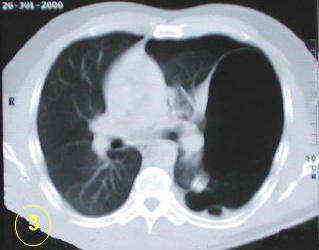

La tomografía computarizada del tórax

y su adecuada interpretación es de gran ayuda diagnóstica

en las patologias del tórax.